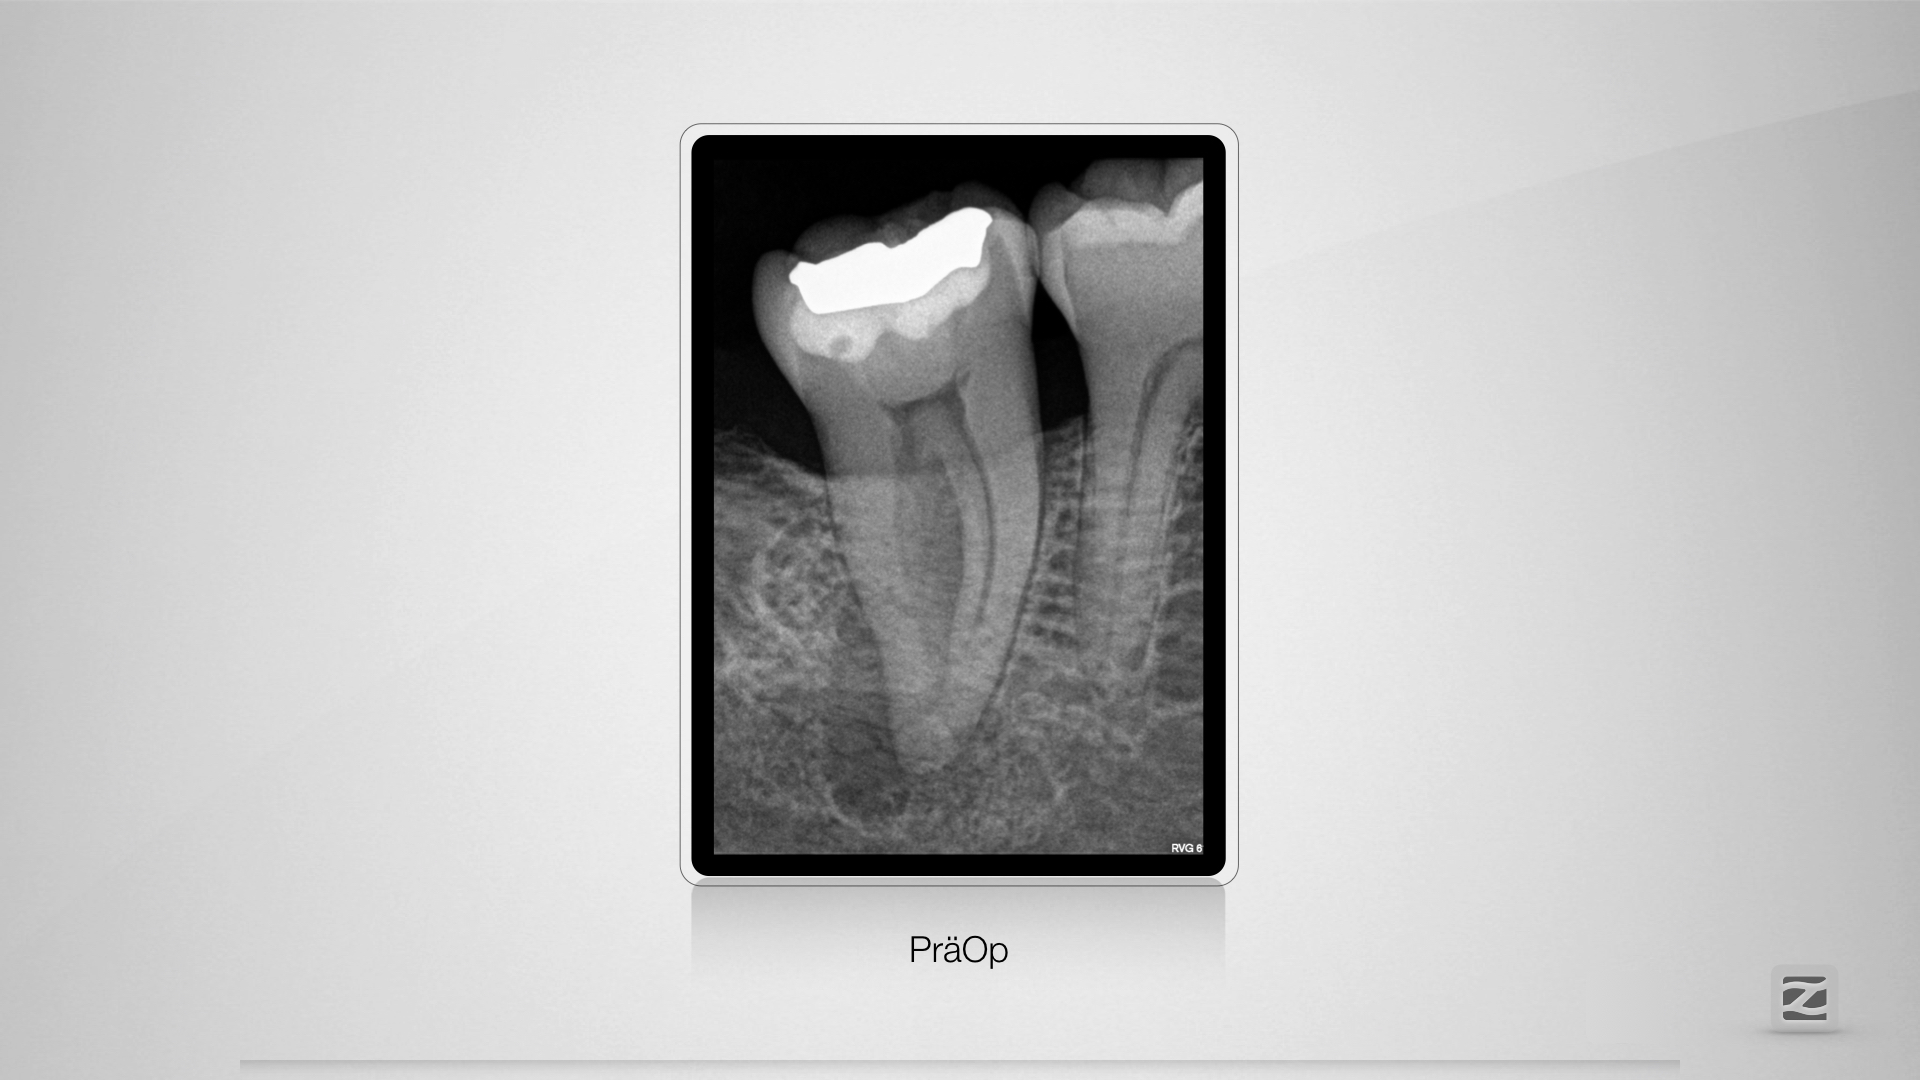

Komplexe Anatomie 47